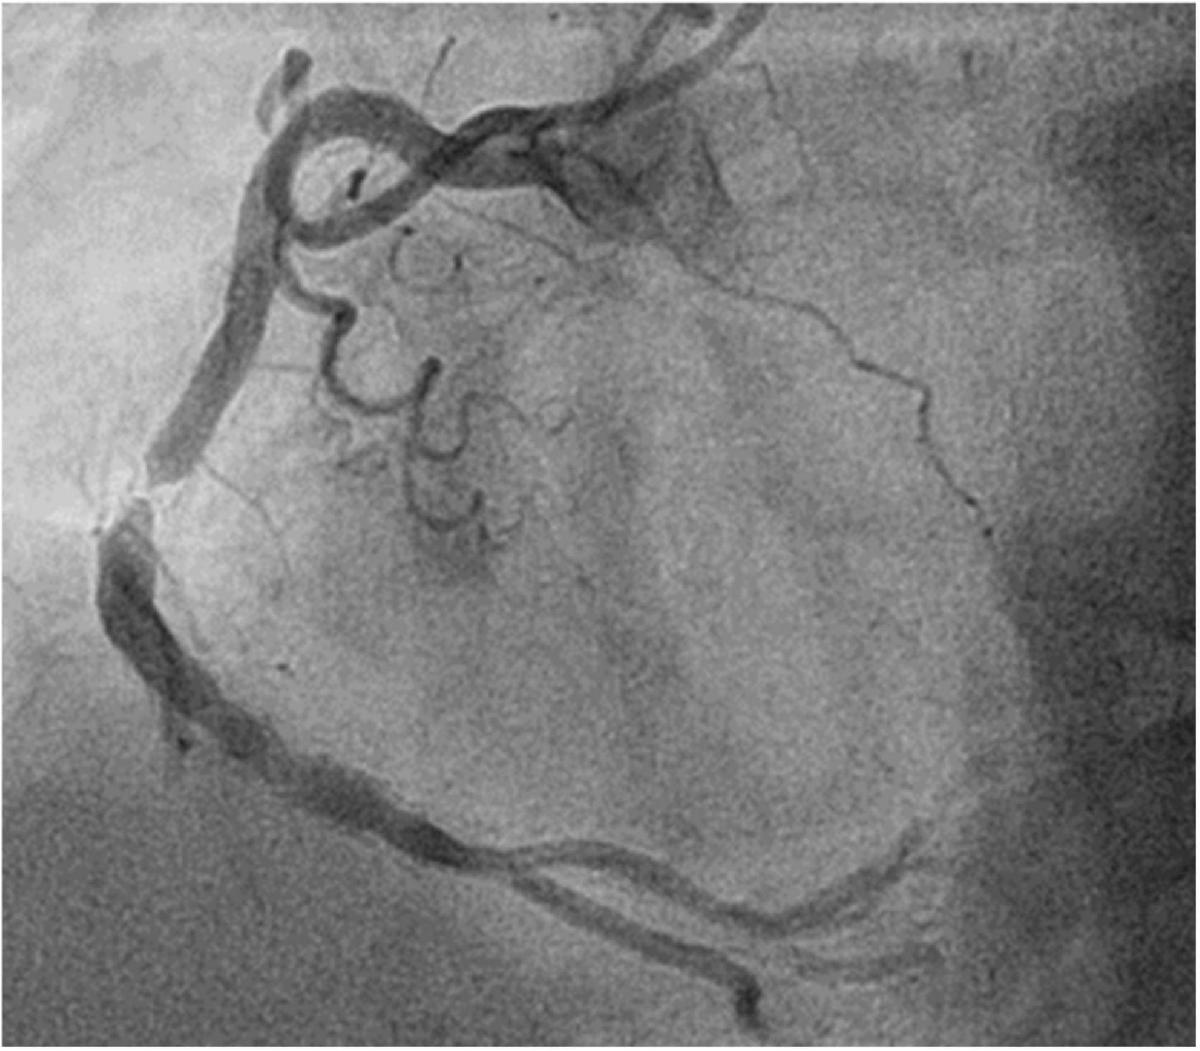

心血管疾病長年位居國人十大死因,其中冠狀動脈疾病是心肌梗塞與猝死的主因。透過心導管手術置入心臟支架,能有效打通阻塞血管,恢復心臟供血。然而,這並非一勞永逸,術後仍存在一個潛在風險—支架再阻塞。

支架再阻塞指血管在置入支架後數月至數年內再次狹窄。主要原因包括,血管內皮細胞過度增生,使支架內膜變厚、動脈硬化進一步惡化,及不良生活習慣如抽菸、血糖控制不佳等,導致血管再次受損。儘管新一代**藥物塗層支架(DES)**已大幅降低再狹窄率(5-10%),但此風險仍不容輕忽。